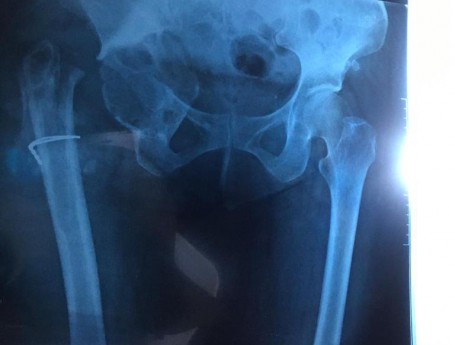

Revision Total Hip Arthroplasty

• Revision Total Hip Arthroplasty